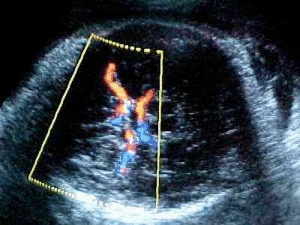

| Zusätzlich hat man die Möglichkeit mittels Doppler-Sonographie, einer speziellen Ultraschall-Untersuchung, die Fließgeschwindigkeit des Blutes in den Hirngefäßen zu messen um damit Einengungen und Ablagerungen an den Gefäßwänden zu erkennen. | |